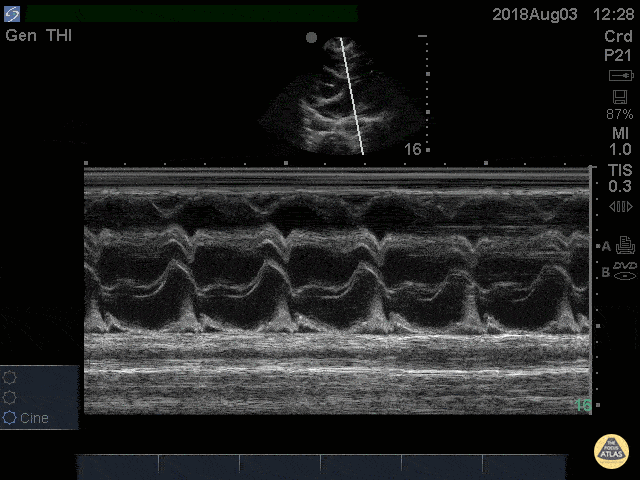

Pericardial Disease - Cardiac Tamponade RV Diastolic Collapse M-mode

41 yo M with history of stage 4 lung cancer presents with AMS and dyspnea, normotensive and tachycardic to 140s. Parasternal long view showed moderate pericardial effusion with RV collapse. With M mode we are able to see the RV wall collapse (top line) corresponds with the mitral valve opening i.e. it occurs during diastole. Even though the patient was normotensive he was taken to the OR for a pericardial window within the hour given this evidence of echocardiographic tamponade. Nathan Kabariti MS4, Dr. Charles Murchison, Dr. John Riggins, Dr. Donald Doukas - Kings County Emergency Medicine